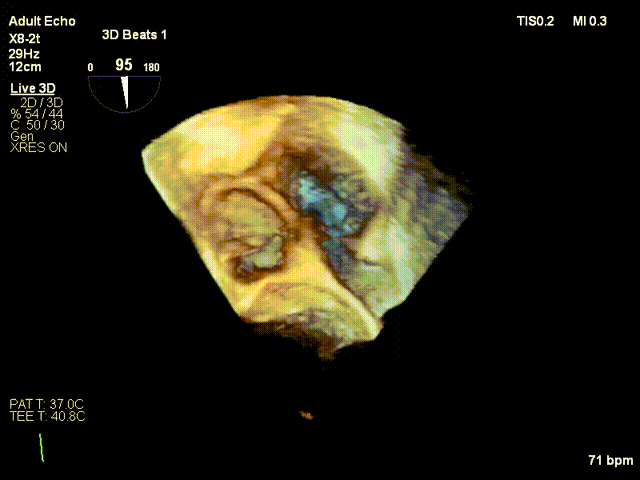

术前术后反流对比:三尖瓣反流4+下降至1+

术前反流

术后反流